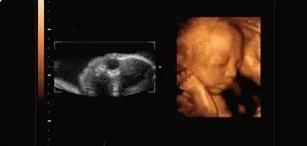

本宝宝有些困了——打哈欠